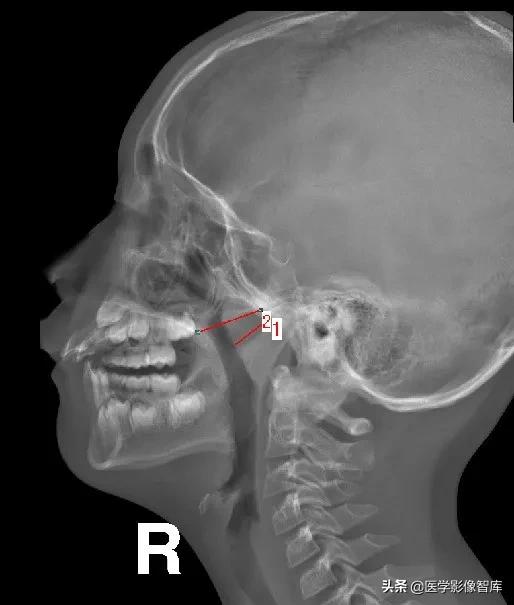

鼻咽侧位片的测量方法(一)

腺样体-鼻咽腔比率A/N值:

腺样体厚度(A)的测量:

腺样体最突点至枕骨斜坡颅外面的垂直距离

>13mm,就会出现鼻咽腔气道变窄,甚至闭塞。

*2长:2.31cm

(1)1987年Elwany提出鼻咽腔的宽度(N)测量方法:

硬腭后端--翼板与颅底交点间距

*1:长:2.61cm

2:长:2.29cm

*3:长:2.72cm

(2)鼻咽腔的宽度(N)测量方法:

N为腺样体最凸部鼻咽腔的宽度,即垂线的反向延长线与硬腭后端或软腭前中部上缘的交点和枕骨斜坡颅外面切线的垂直距离。

1:长:1.82cm

*2:长:2.71cm

*2:长:2.57cm